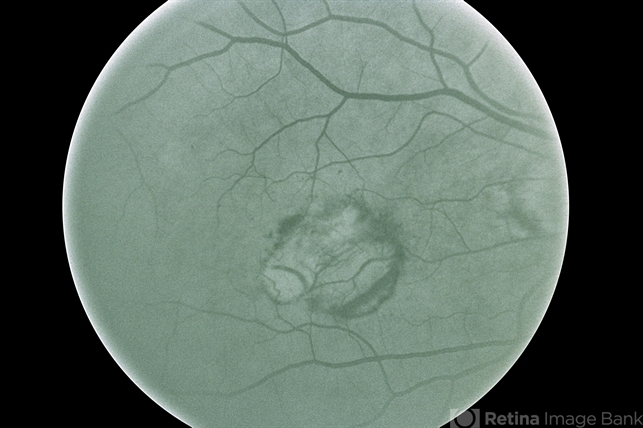

- laser treatment, treated recurrence

- No history, this is before treatment.